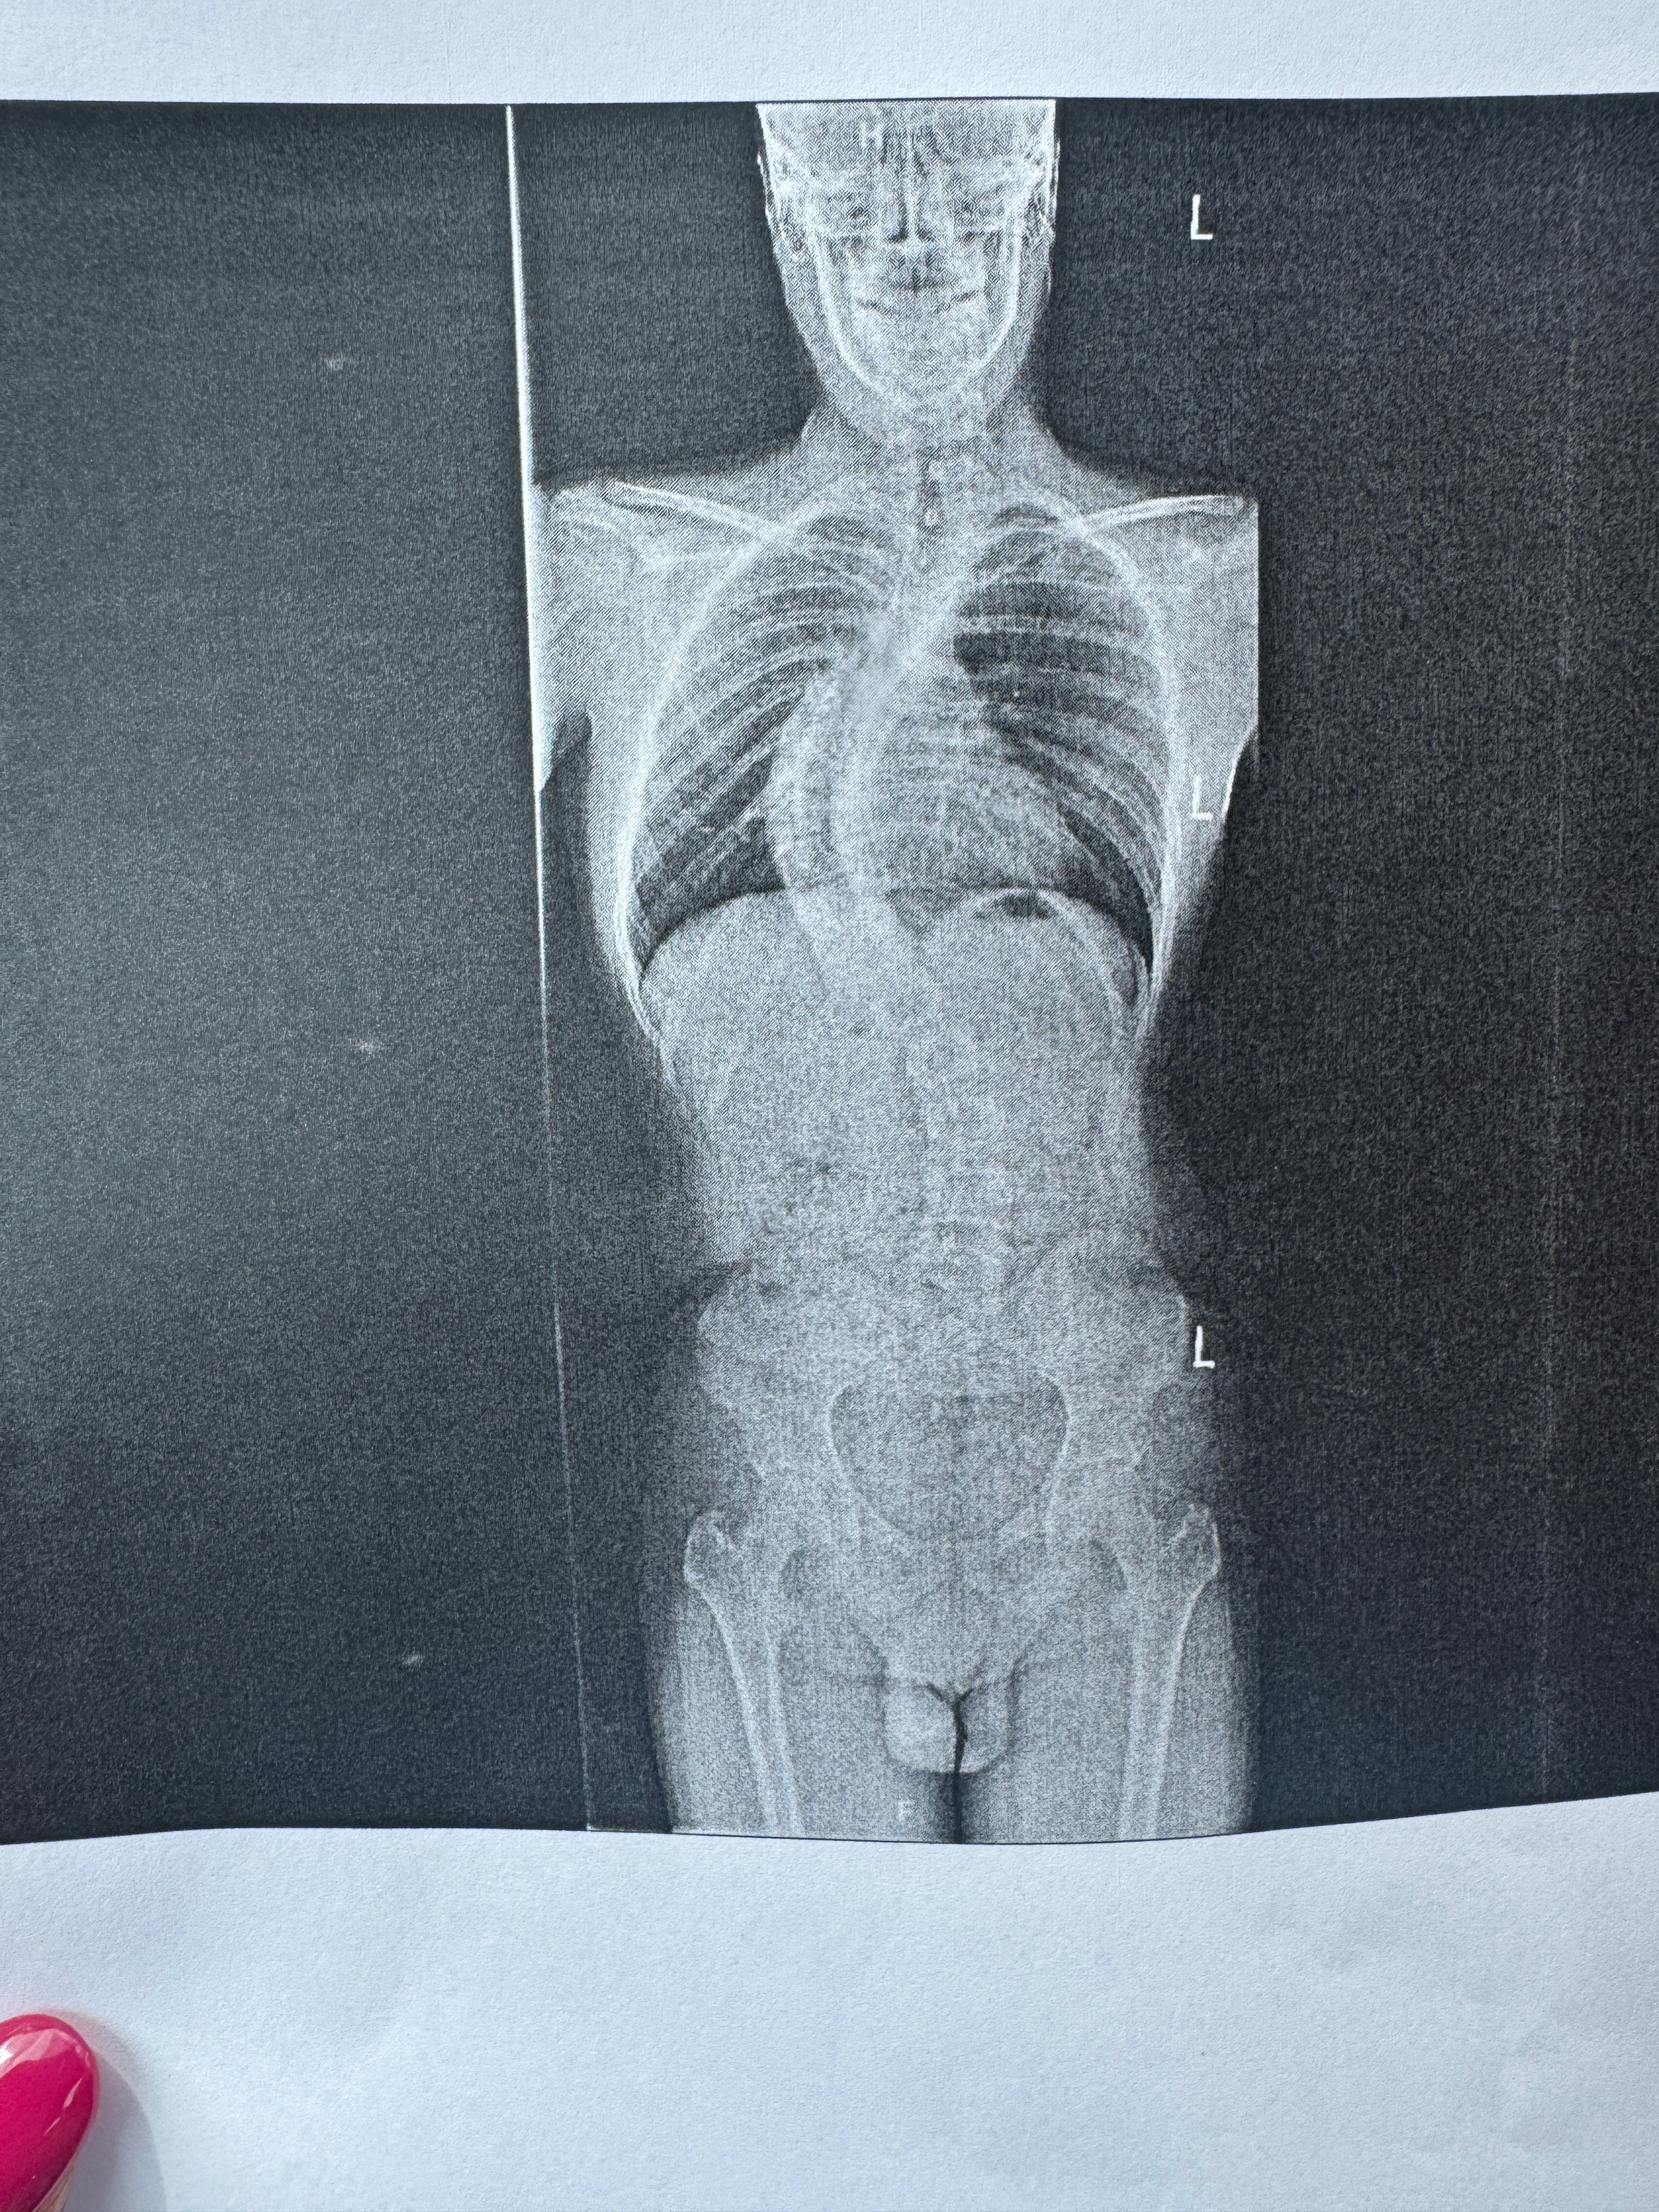

The cover photos below are of a case of severe scoliosis in Jaden. Jaden is a 17 year old autistic student in the 10th grade at Annville-Cleona, who truly needs us right now. His spine curvature went from 65° in May to 75° in August, so this issue is progressing rapidly.

The surgeon has recommended that they do rods, plates, screws, and a bone graft to hold everything in place. the worst part is that this may not be the only surgery he has to endure in the next few years.